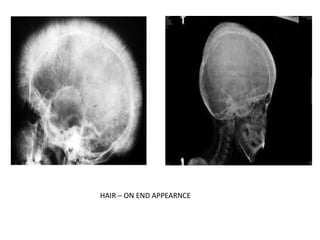

Hemolytic anemias – most striking in thalassemia. Diploic space is widened with striking

radial striations ( “hair – on –end”). PNS may be completely obliterated.

HAIR – ON END APPEARNCE